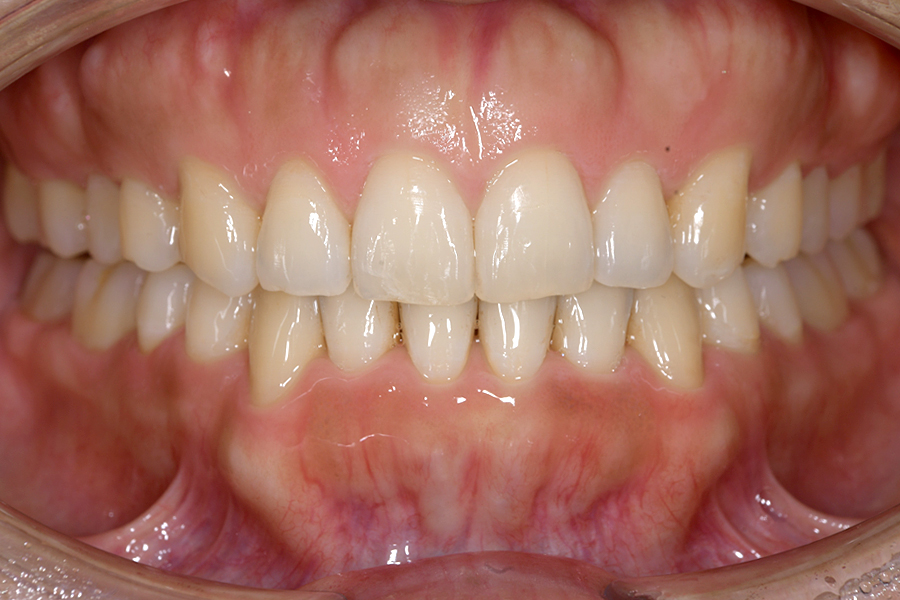

| 主訴 | 見た目を治したい、歯を白くしたい |

|---|---|

| 治療期間 | 1年6か月 |

| 治療費 | マウスピース矯正と ホームホワイトニングセット 1,022,350円(税込) |

| 治療内容 | 目立ちにくいマウスピース矯正 (非抜歯矯正) 歯と歯の間に隙間をつくることにより、歯列弓を広げながら治療を行いました。 また矯正用マウスピースをトレー代わりにし、ジェルを入れてホームホワイトニングを同時に行っております。 |

| 治療のリスク | ・後戻りする可能性があるのでリテーナーを最低でも矯正期間以上はつける必要があります。 ・ホワイトニング後、一時的に痛みが出る場合があります。 |